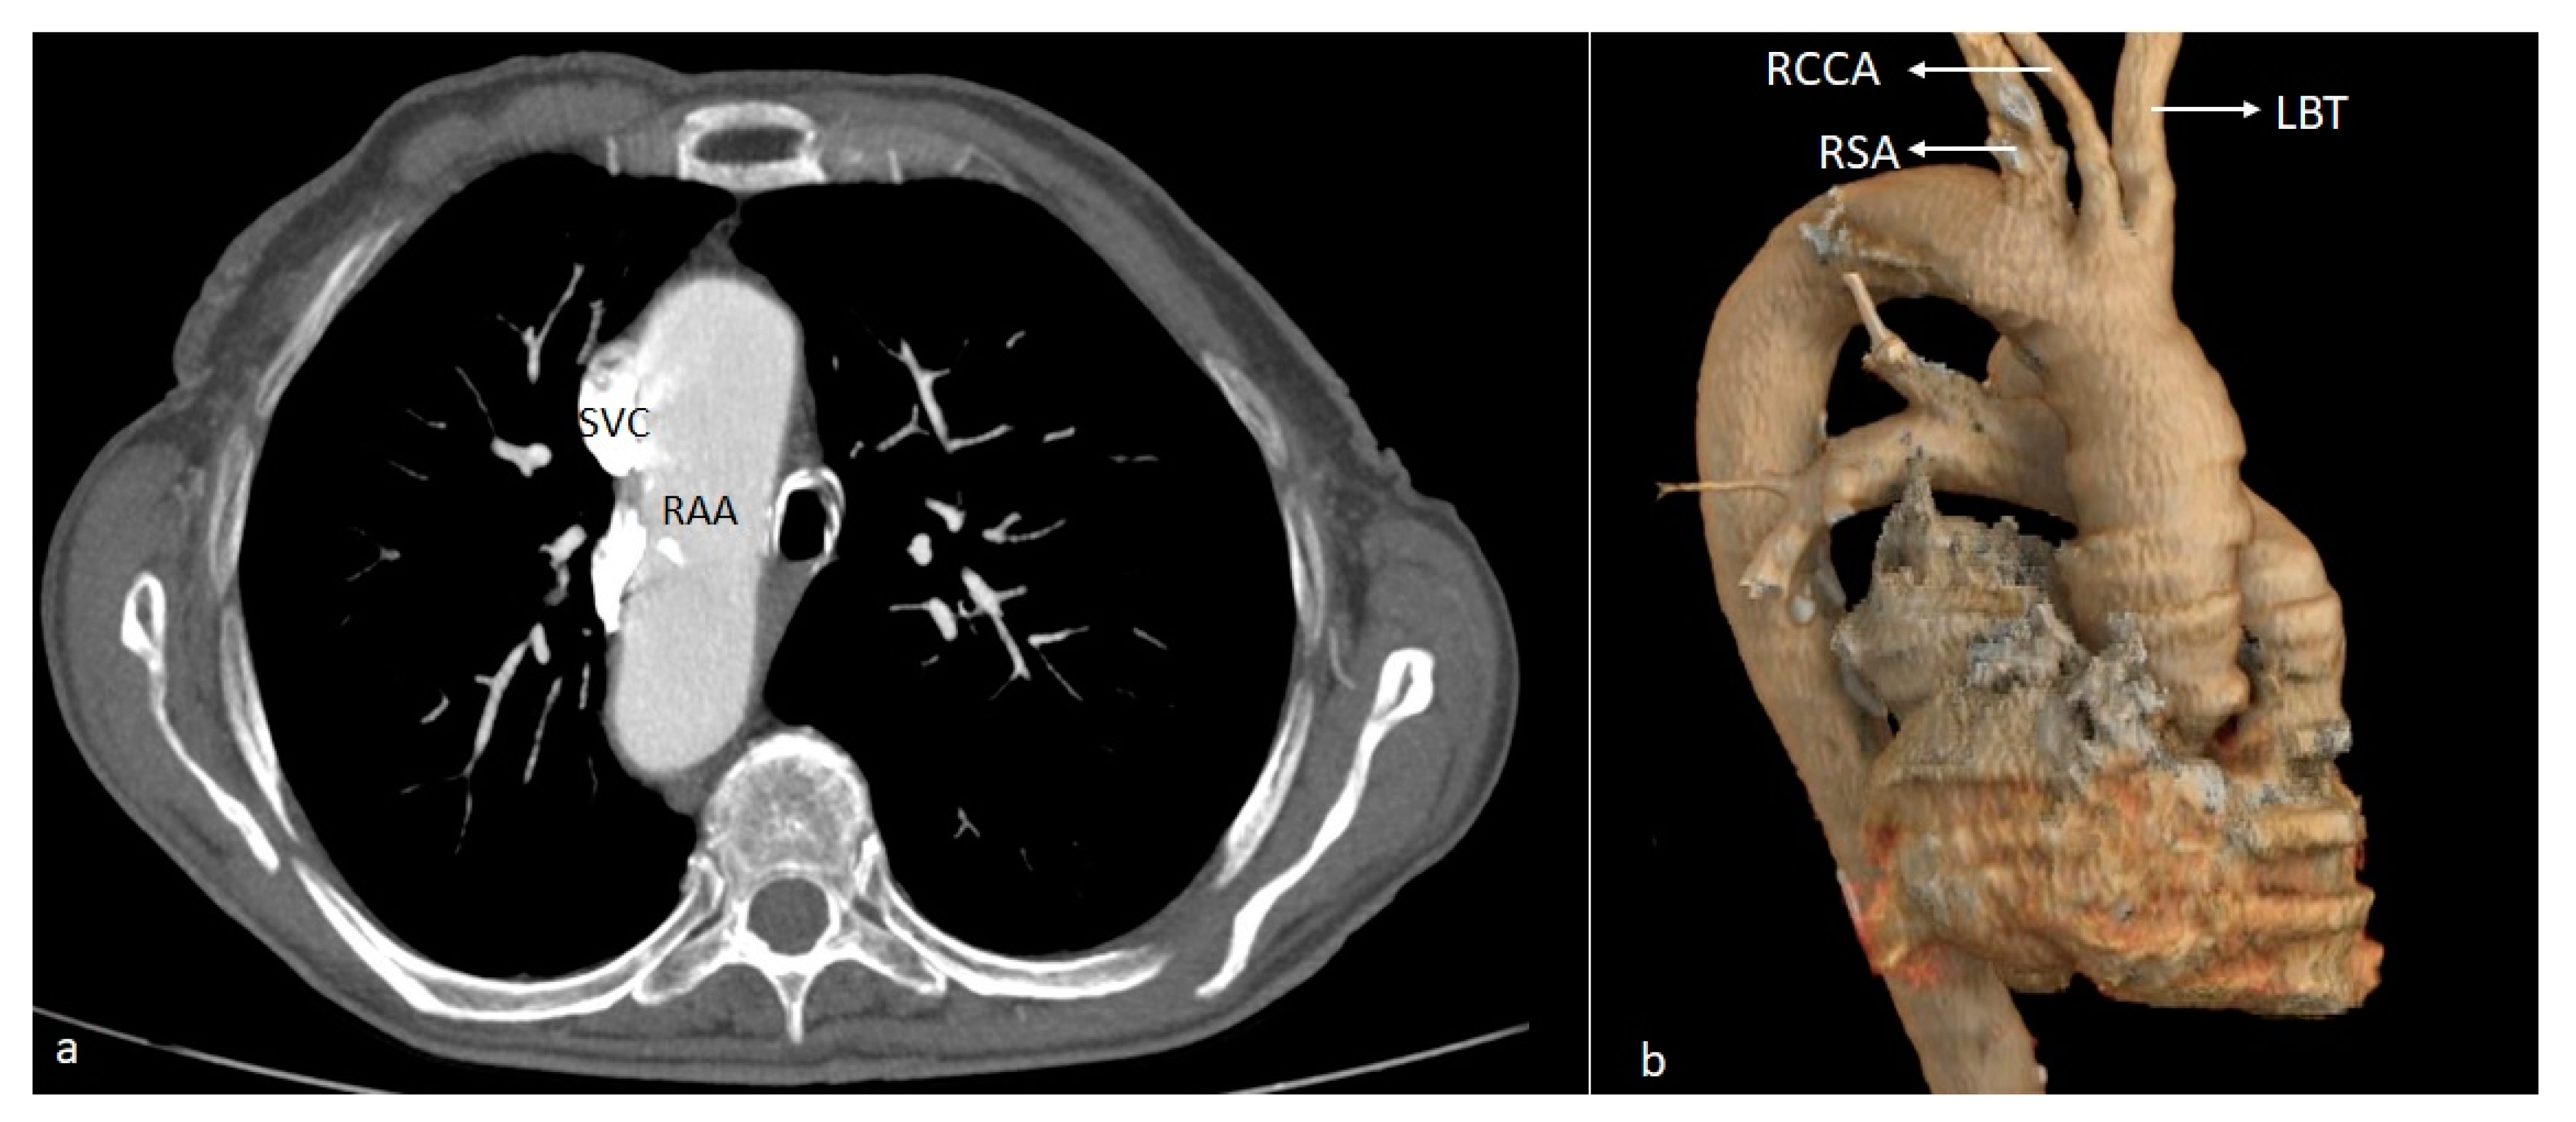

| RAA | Right aortic arch |

| RCCA | Right common carotid artery |

| SVC | Superior vena cava |

| BT | Brachiocephalic trunk |

| LBT | Left brachiocephalic trunk |